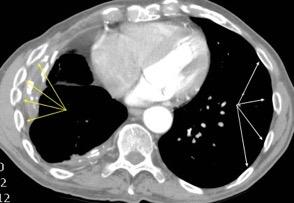

> Grasa Extrapleural (60-80%)

Engrosamiento de la pleura parietal 36/ 59 exudados (61%) 56% de D. paraneumónicos 100% de empiemas Especificidad.. 96%.

Exudado versus trasudado.

Aquino SL, et al. Pleural exudates and transudates: diagnosis with contrast-enhanced CT. Radiology 1994

Signo de la Pleura separada “Split pleural sign”

Capas pleurales de grosor uniforme realzadas por el contraste

Dr. César Pedrosa

No específico de empiema. Indica “exudado”. 68% de pacientes con empiema pleural.

Capas pleurales de grosor uniforme

Realce grasa extrapleural (30%)

> Grasa Extrapleural. (60-80%)

Kraus GJ. Split pleural sign. Radiology 2007

Pleural visceral 50%

Pleural parietal 100%